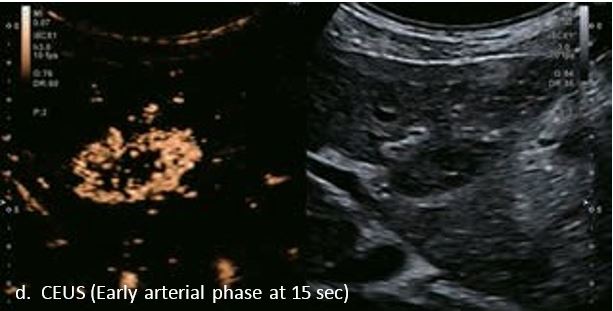

LI-RADS 5 з декількома ГЦК

У 70-річної жінки з цирозом печінки, хворої на вірусний гепатит С, у правій частці печінки виявлено вогнище ураження розміром 23 мм. Детальна судинна структура та підживлююча судина чітко візуалізуються за допомогою CEUS на ранній артеріальній фазі та під час портальної венозної фази, а ураження є ізопідсилюючим. Це ураження є типовим для LI-RADS 5 за своїм розміром, гіперпосиленням в артеріальній фазі та пізнім і помірним вимиванням, що спостерігається через 3 хвилини після ін'єкції.

Малюнок 12